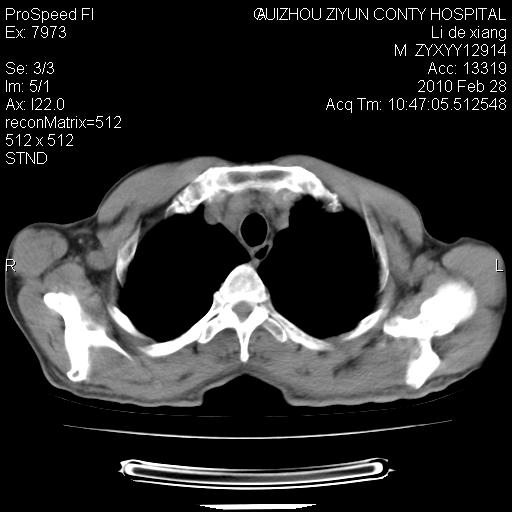

标题: CT24776:男 71Y 咳嗽咳痰胸痛两月,伴声音嘶哑。 [打印本页]

标题: CT24776:男 71Y 咳嗽咳痰胸痛两月,伴声音嘶哑。

纵膈淋巴结肿大 不除外占位性阻塞

左上叶支气管狭窄,阻塞性病变,肺门肿块,纵隔及肺门淋巴结增大,中央性肺癌

左肺中央型肺癌并阻塞性改变、纵膈 淋巴结转移